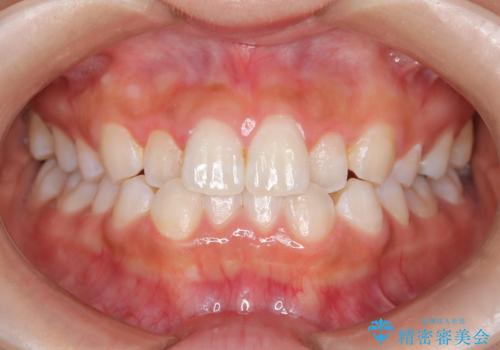

- 子供のころに矯正治療をされていたが、後戻りをしてしまったという20代女性の患者様です。上顎左右の2番が、咬合時に下顎の歯よりも内側に入っているクロスバイトという状態でした。奥歯の咬合関係は変えずに、マウスピース矯正にて前歯の並びを綺麗なアーチに仕上げました。再度後戻りしてしまうリスクを軽減させるために、リテーナー(保定装置)をお渡ししています。